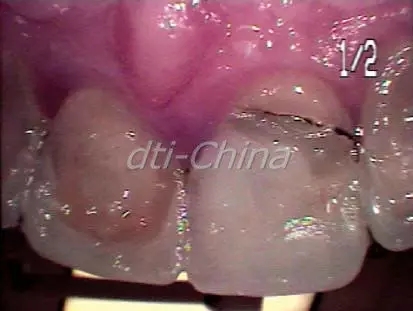

患者是一個30歲健康男性, 來診所檢查失去功能的上頜右中切牙, 過去在1993年的一次足球意外中因臉部受到肘擊導(dǎo)致上頜右中切牙的外傷,在事故大約一周之后, 對患者的牙齒進行了根管治療,最后牙齒開始變色而且越來越不整齊(圖1)。影像檢查發(fā)現(xiàn)內(nèi)吸收。通過臨床診斷,發(fā)現(xiàn)所有其它的上下前牙都完好無損,牙周檢查顯示健康的牙齦組織,患者擔心他的前牙會意外斷裂, 并希望立即替換患牙。